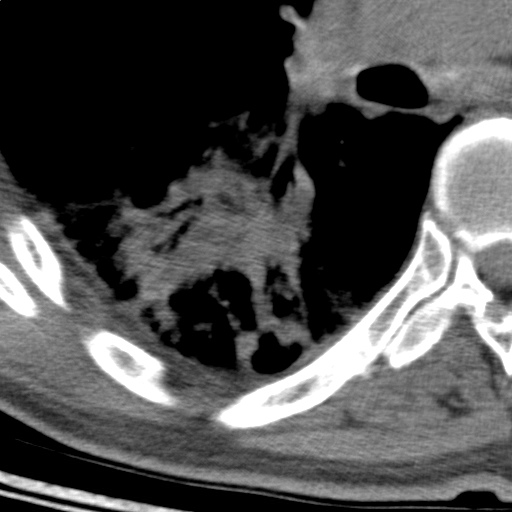

以下是引用随光逐影在2009-5-1 13:53:00的发言:[br]考虑为:1)两肺血行播散型肺结核;2)右肺下叶炎症感染。3)右侧胸膜增厚。